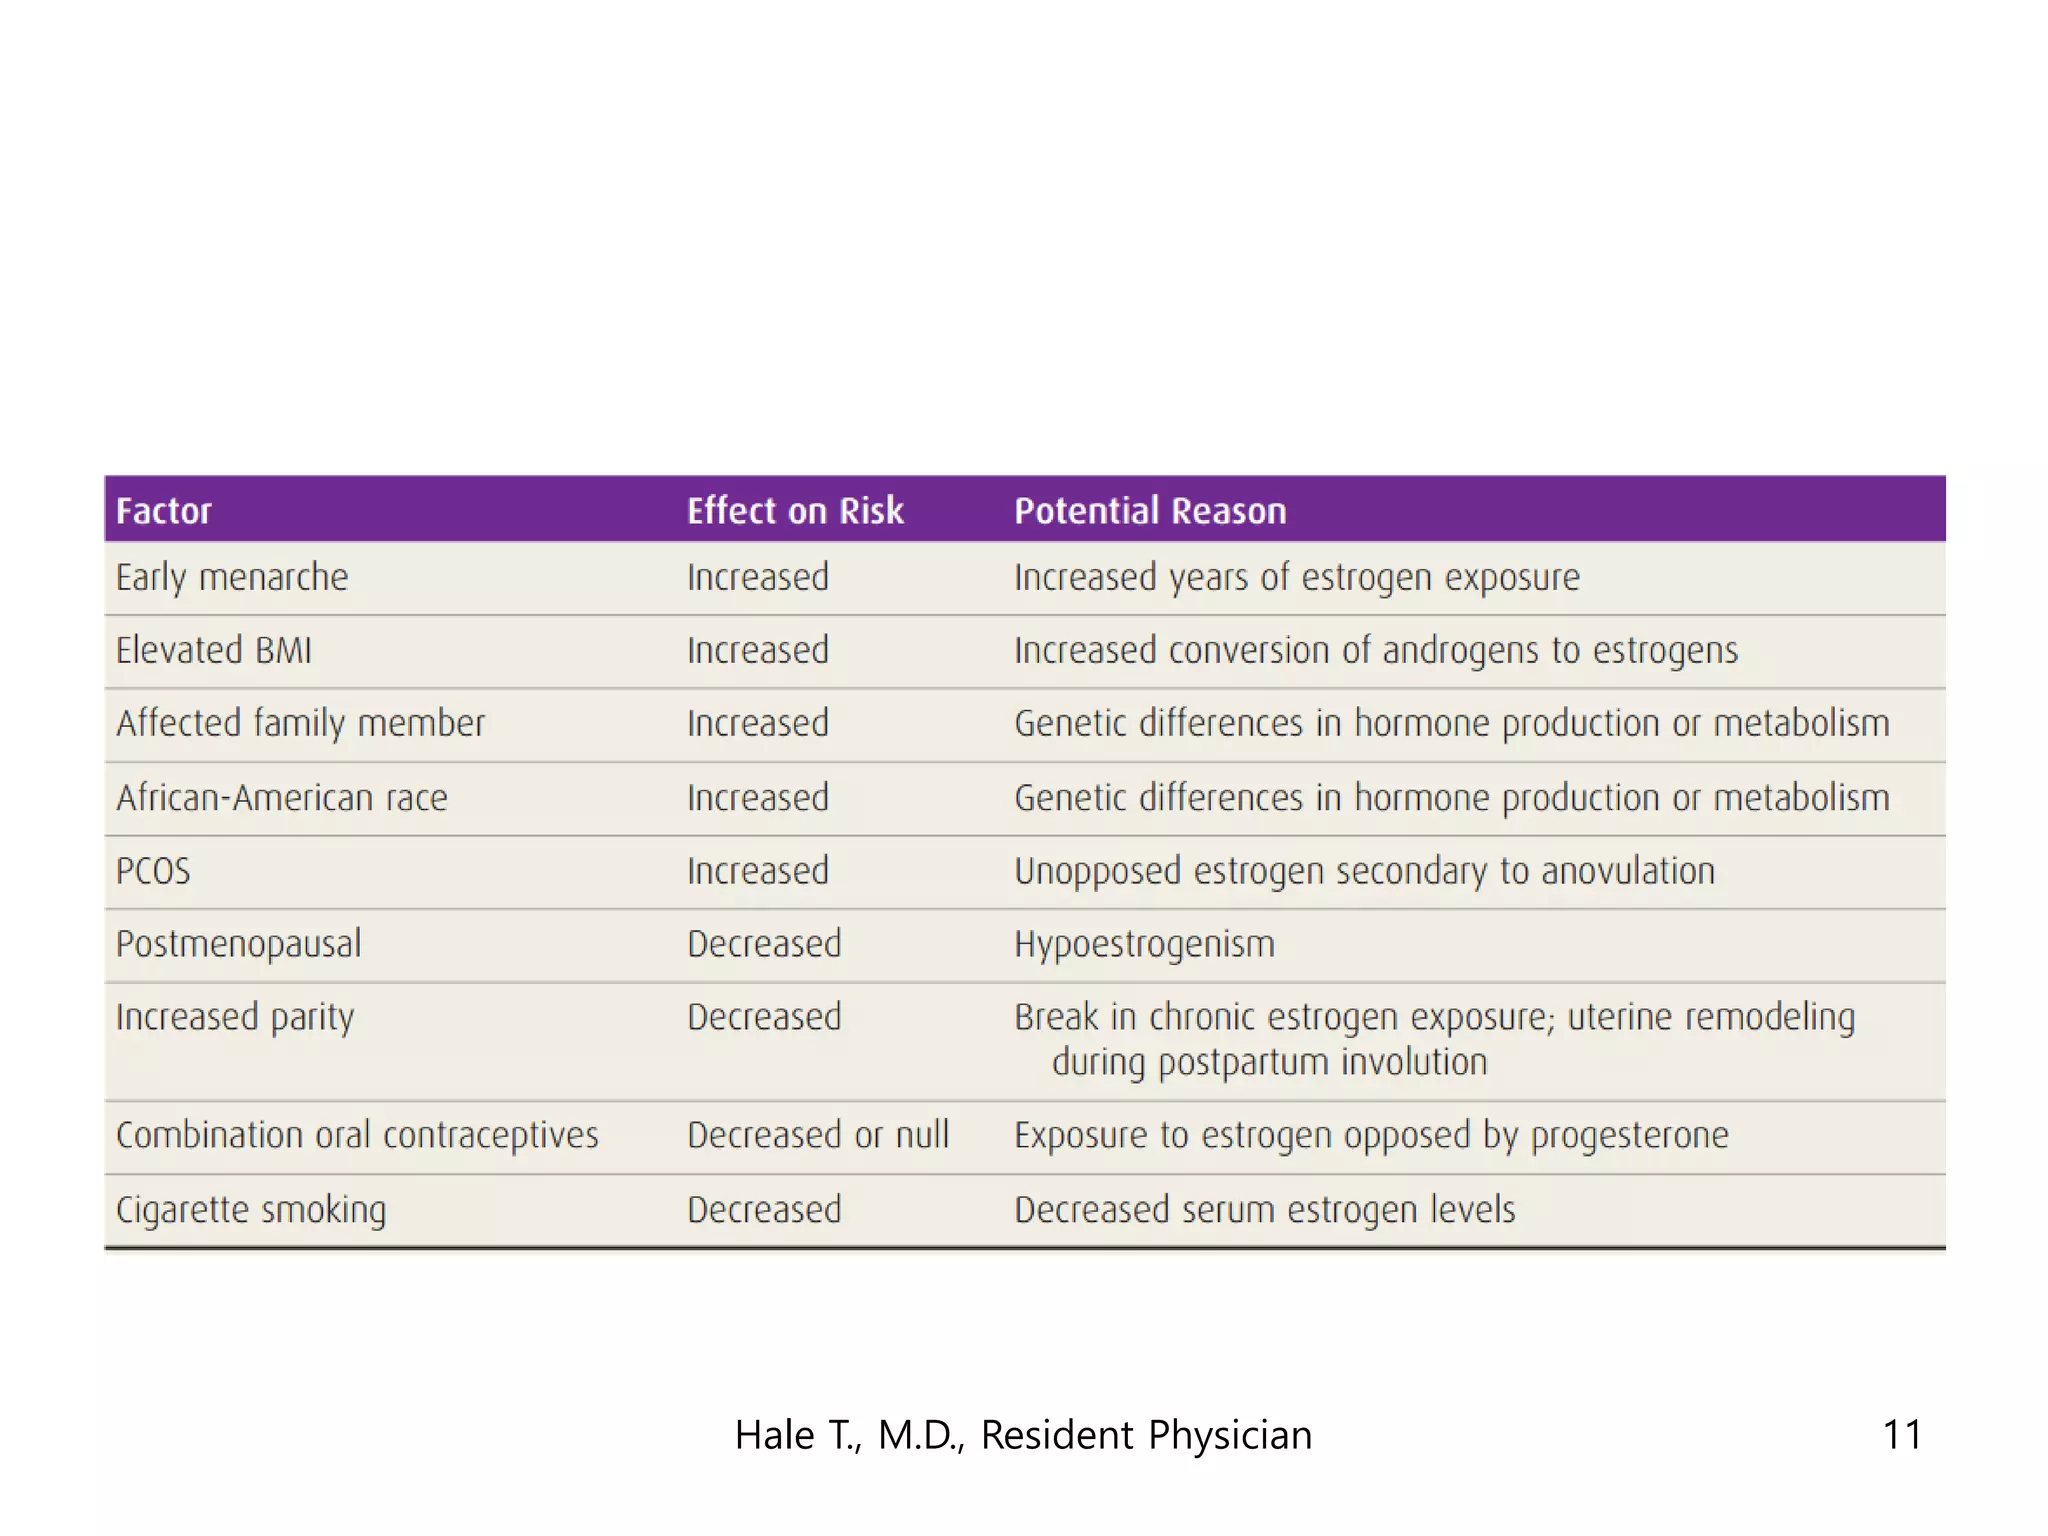

This document discusses myomas (uterine fibroids). It notes that myomas are benign smooth muscle tumors that originate in the uterus and are sensitive to estrogen and progesterone. Symptoms can include bleeding, pain, pressure, and infertility. Diagnosis is usually made through imaging like ultrasound or MRI. Treatment options include observation, drug therapy, uterine artery embolization, or surgical removal of the fibroids. The document also discusses complications that can arise if fibroids are present during pregnancy, such as pain, bleeding, preterm birth, and pregnancy loss.